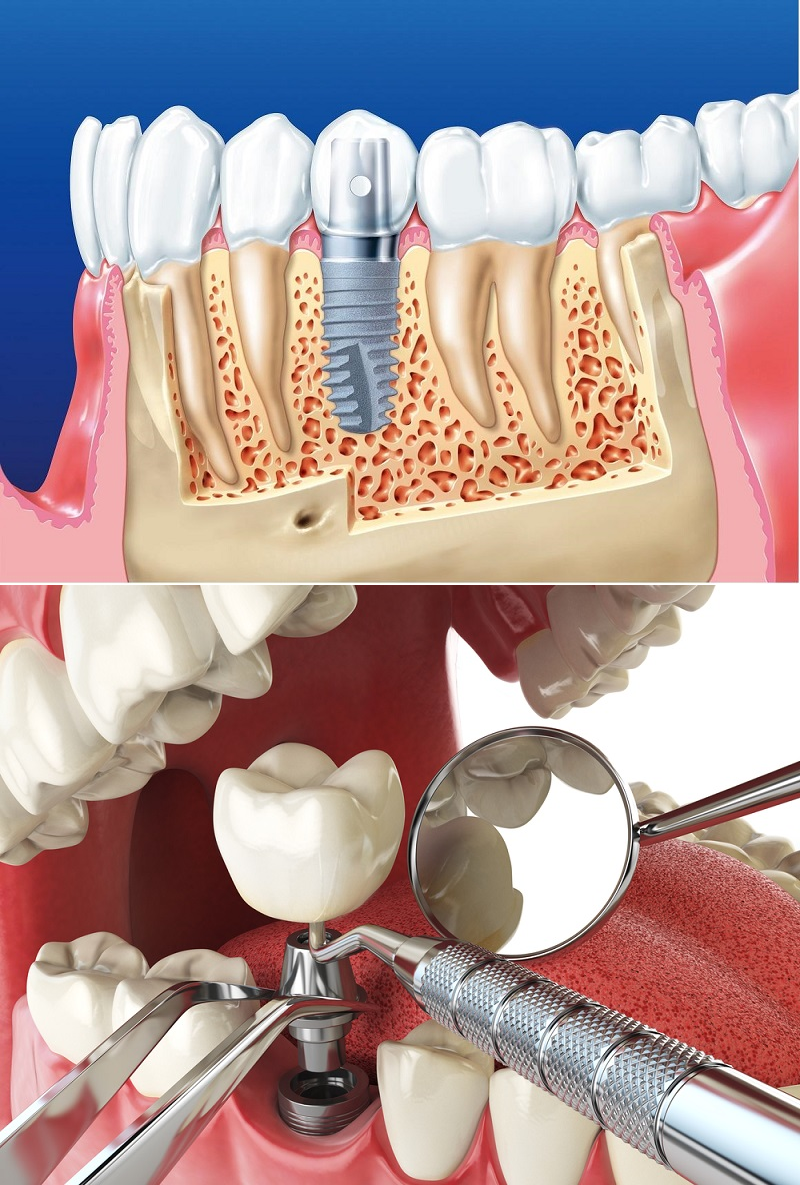

Современная стоматология: Железные зубные импланты